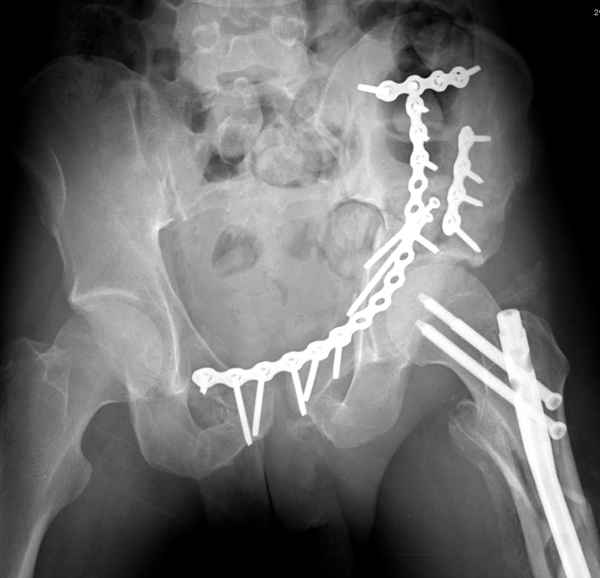

высылаю дополнительно сканы.

итак, второй вариант: высокий двухколонный с вовлечением КПС... Ни одно из основных повреждений не репонировано, кроме задней стенки. Скорее всего попытка реконструкции вертлуги сейчас будет очень травматичной и не очень эфективной, т.е. вероятный риск более значим, чем ожидаемая польза... Лучше подождать, и потом сразу эндопротез

Когда перелом не получается отнести к какому либо типу - эффективнее всего описать более детально. В дальнейшем проще бывает сортировать, и что важнее - "руководство к действию" бывает более обоснованным. В данном случае графа клинического диагноза может выглядеть так: Застарелый разрыв правого крестцово-подвздошного сочленения, консолидирующиеся со смещением переломы крыла и тела правой подвздошной кости, обеих колонн и задней гемисферы правой вертлужной впадины. Состояние после остеосинтеза.

мы имеем дело с полупоперечным переломом у которого отломался задний край или его отломали, превратив перелом в полный двухколонный.

Из того минимума, что представлено, мне кажется, мы имеем дело с двухколонным переломом вертлужной впадины. Обычно медиальный (центральный) "вывих" головки встречаются в сложных двухколонных переломах со смещением.

По-моему, надо готовить больного к будущей артропластике, но без опоры на задний столб невозможно удержать протез. Опорная конструкция (кольца и т.д.) должны иметь опору, и поэтому мы бы сделали реостеосинтез задним доступом. При надобности остеотомия и рутинная фиксация с межколонными винтами.

Здесь несколько вариантов двухколонных свежих переломов, которые были оперированы из одного-заднего, а также из двух: переднего и заднего доступов.